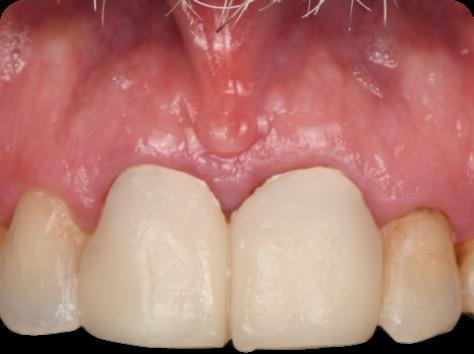

This case was performed by Dr Homa Zadeh, DDS, PhD, a respected leader in periodontology and implant dentistry. Dr Zadeh’s approach emphasizes biologically driven protocols and evidence-based techniques, making this case a strong example of clinical excellence using the Tapered Pro Conical system. It involves the replacement of two front anterior teeth after they fractured off and the full restoration process.

Fig 1. Patient anterior situation. Two anterior crowns fractured off.

Fig 5. Central incisors extracted using minimally invasive protocol. Alveolar bone and gingival tissues were intact after extraction

Fig 6. BioHorizons Tapered Pro Conical implants of 3.8 x 15mm placed according to the plan.

Fig 7. Implants immediately after installation.

Fig 8. Scanbody installation for custom abutment and definite restoration fabrication.

Fig 9. Periapical radiograph for verification of proper seating of the scanbodies.

Fig

Fig 11. Bone graft filling the horizontal gap between socket and implants.

Fig 12. Screw-retained provisional restoration placed into implants, with LPRF placed to protect graft material.

Fig 13. Radiograph of implants, grafts and Provisionals.

Fig 14. Clinical view at two days post-operative visit.

Fig 15. Clinical view at two days post-operative visit

Fig 16. Patient’s smile after implantation and previsualization